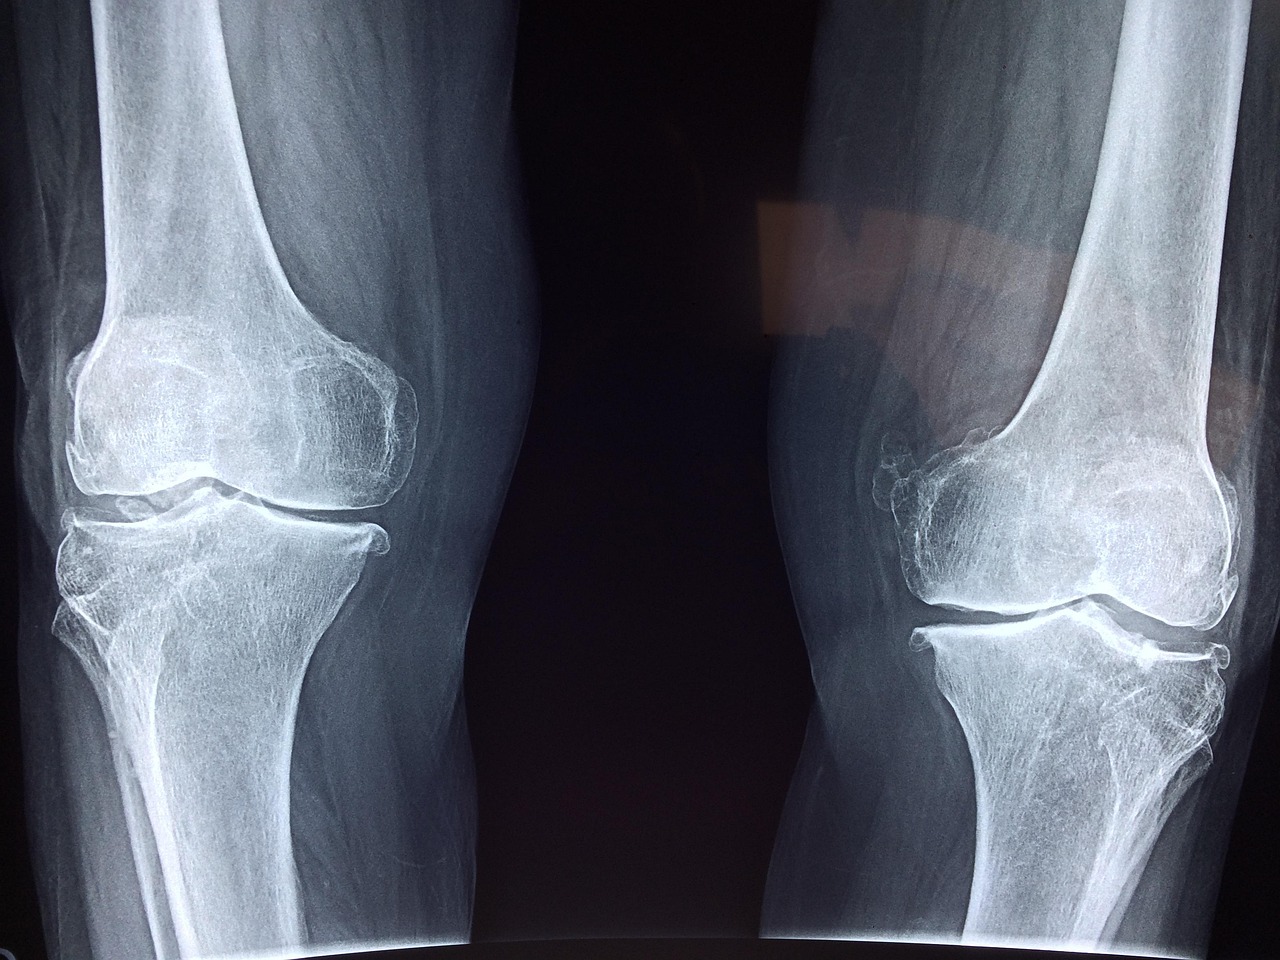

Understanding Joint Mechanics

Our understanding of running must consider the mechanical dynamics of the knees. The knee joint is a complex structure comprised of bones, cartilage, ligaments, and tendons that work in harmony during physical activity. When running, the force exerted on this joint can be significant, but the body is equipped to handle this when conditioned properly. Notably, the cartilage acts as a cushion that absorbs impact, which helps to protect the underlying bones. Research has shown that with consistent running, the knee can adapt, becoming stronger and more resistant to injury. Interestingly, runners often possess higher levels of proprioception and coordination, which enhances their performance and can mitigate the risks of injury. Different running styles, such as heel striking versus midfoot striking, can alter the distribution of forces across the knee. Identifying an ideal running form is critical. Additionally, the choice of running surfaces can significantly affect knee stress. Softer surfaces such as grass or a running track typically reduce impact forces compared to harder surfaces like concrete. Thus, educating runners about biomechanics can help them avoid the myths surrounding knee health.